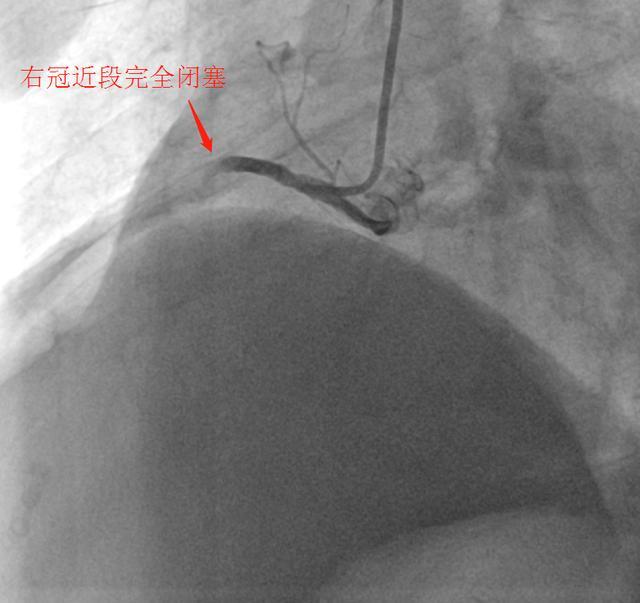

导管室内,医护人员凭借丰富的救治经验和精湛的操作技术,默契配合开展介入治疗。导丝精准穿过堵塞血管,支架顺利植入,闭塞的血管被成功开通,缺血的心肌重新获得血液灌注。从转运途中启动救治预案,到手术顺利完成,整个流程环环相扣、分秒必争,体现了高效有序的应急能力。

(▲术前)